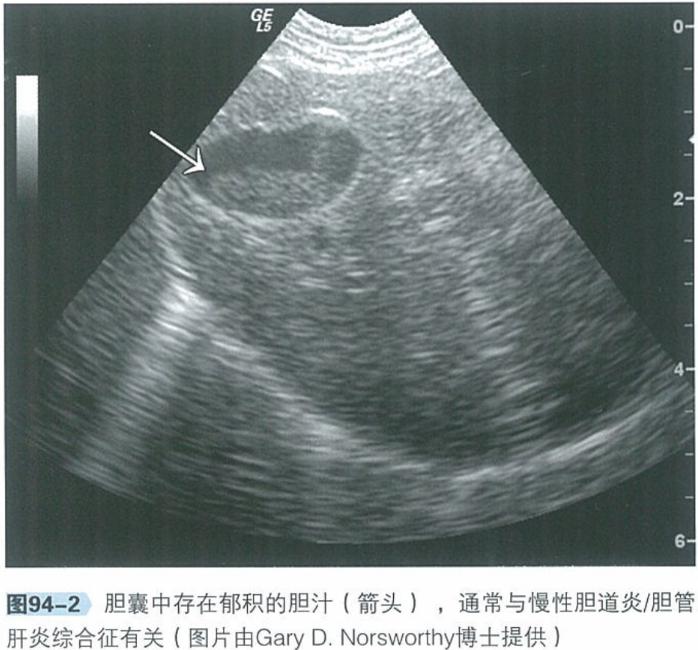

b.腹部超声:腹部超声是检查肝脏、胆管系统及胰腺实质结构极为有用的工具。肝脏回声通常正常,胆管及胆囊可见异常,包括胆总管、胆囊或肝内胆管扩张、部分或完全阻塞,胆汁淤积。